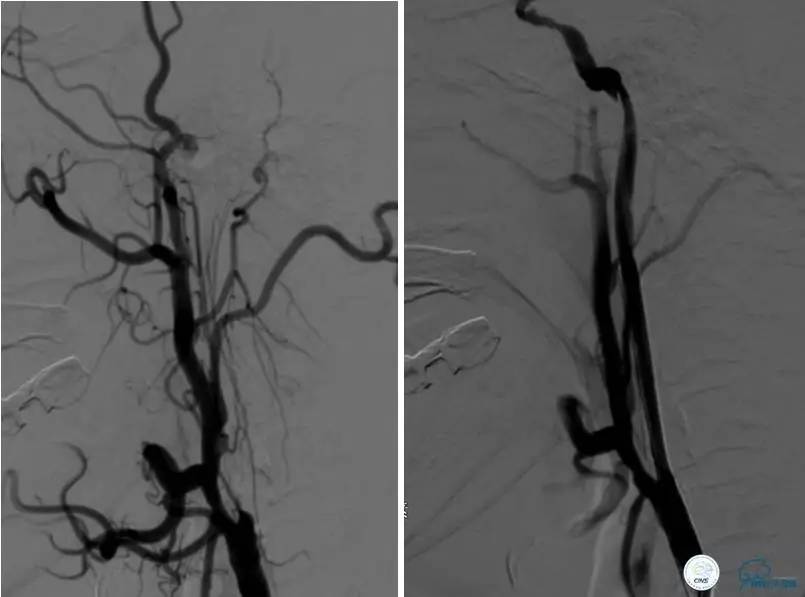

▼DSA示右侧椎动脉发育低下,弥漫性狭窄,可以看到左侧椎动脉反流,因此判断左侧椎动脉V4段CTO。

治疗:

微导丝穿过闭塞段,微导管造影,球扩闭塞段,置入Wingspan支架,血流完全恢复正常。

患者术后2天再次出现卒中发作,药物治疗好转,此后病情稳定。半年后复查DSA,见支架闭塞,侧支循环开放。患者一般情况好,mRS:1分。